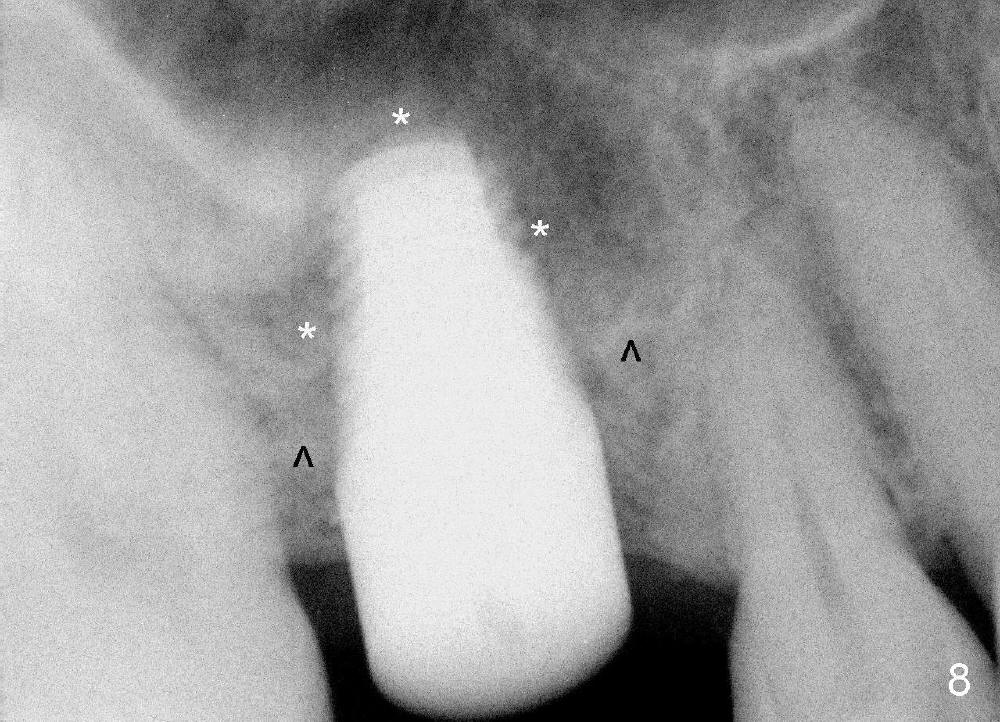

Our experience demonstrates higher failure rate associated with shorter implant in this situation. The depth of the osteotomy is then increased to 14 mm using the same series of osteotomes and taps. The bone at the top of the osteotomy finally wears off when the last tap is applied (7x17 mm). But the sinus membrane is intact. Osteogen is pushed into the osteotomy before placing a 7x14 mm implant with insertion torque > 60 Ncm (Fig.5). The implant contacts the gingiva tightly; no suture is necessary. There is no intra- or postop nasal hemorrhage. The wound heals 8 days postop (Fig.6). There is bone surrounding the apical portion of the implant in the sinus (Fig.7,8 *) 3.5 months postop. The implant is stable. There appears no crestal bone resorption 7.5 months post cementation (Fig.9 ^). Sinus lift is visible 16 months post cementation (Fig.10 (trimmed panoramic X-ray) arrowheads). There is discomfort between #2 and 3, probably due to poor oral hygiene. There is no deep pocket or bone loss (Fig.11, 26 months post cementation).